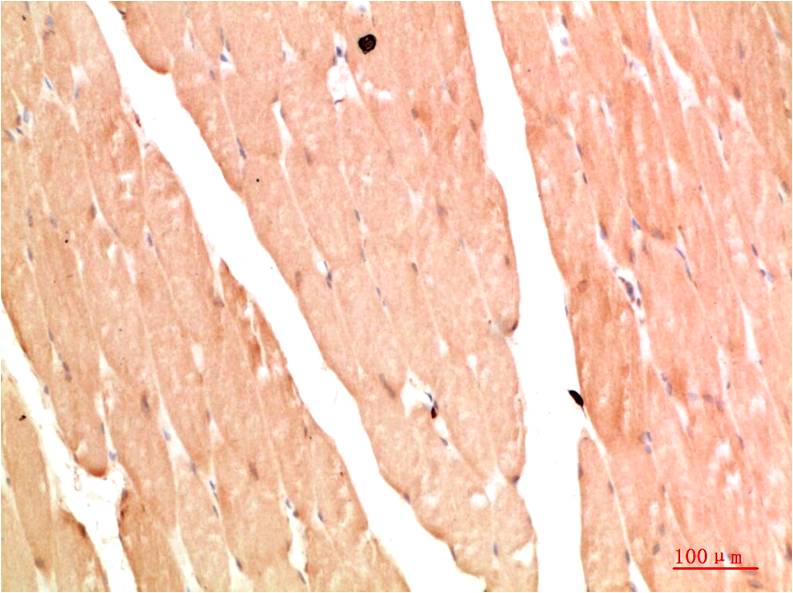

IkB α Rabbit Polyclonal Antibody

Applications :WB, IHC

| Recommended dilutions: | WB 1:500-2,000 IHC 1:50-300 |